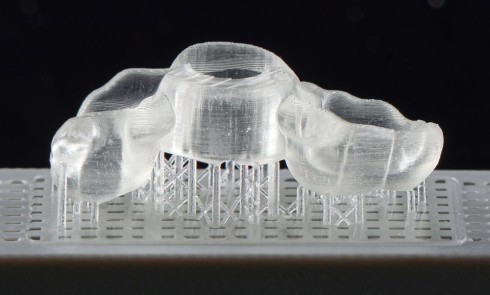

La révolution numérique a désormais touché le monde de l’odontologie, lequel connaît une transformation rapide. De nouveaux outils ont permis...L’impression 3D en prothèse amovible complète

La thérapeutique de l’édentement total est actuellement renouvelée par les apports du numérique et de la CFAO. Grâce à eux,...L’impression 3D chairside : applications et perspectives

Ces dernières années, les avancées technologiques ont permis l’essor de la conception et fabrication assistées par ordinateur (CFAO) et de...La mise en esthétique immédiate 100 % numérique